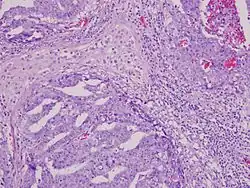

The differential diagnosis of testicular cancer requires examining the histology of tissue obtained from an inguinal orchiectomy—that is, surgical excision of the entire testis along with attached structures (epididymis and spermatic cord). A biopsy should not be performed, as it raises the risk of spreading cancer cells into the scrotum.[28]

After removal, the testicle is fixed with Bouin's solution[33][34] because it better conserves some morphological details such as nuclear conformation. Then the testicular tumor is staged by a pathologist according to the TNM Classification of Malignant Tumors as published in the AJCC Cancer Staging Manual. Testicular cancer is categorized as being in one of three stages (which have subclassifications). The size of the tumor in the testis is irrelevant to staging.[35] In broad terms, testicular cancer is staged as follows:

Although testicular cancer can be derived from any cell type found in the testicles, more than 95% of testicular cancers are germ cell tumors (GCTs). Most of the remaining 5% are sex cord–gonadal stromal tumours derived from Leydig cells or Sertoli cells. A correct diagnosis is necessary to ensure the most effective and appropriate treatment. To some extent, this can be done via blood tests for tumor markers, but definitive diagnosis requires examination of the histology of a specimen by a pathologist. Testicular tumors are best classified by radical inguinal orchiectomy, which allows for histologic evaluation of the whole testicle and provides local tumor control.[39]